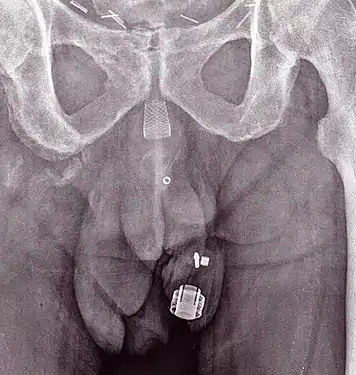

An X-ray image of implanted ZSI 375. The device is deactivated – the spring is compressed below the top of the cylinder. Patient is incontinent.